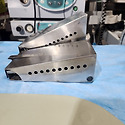

| Symmetry® Ferguson Gall Stone | 최웅범 | 13 | 25.04.09 |